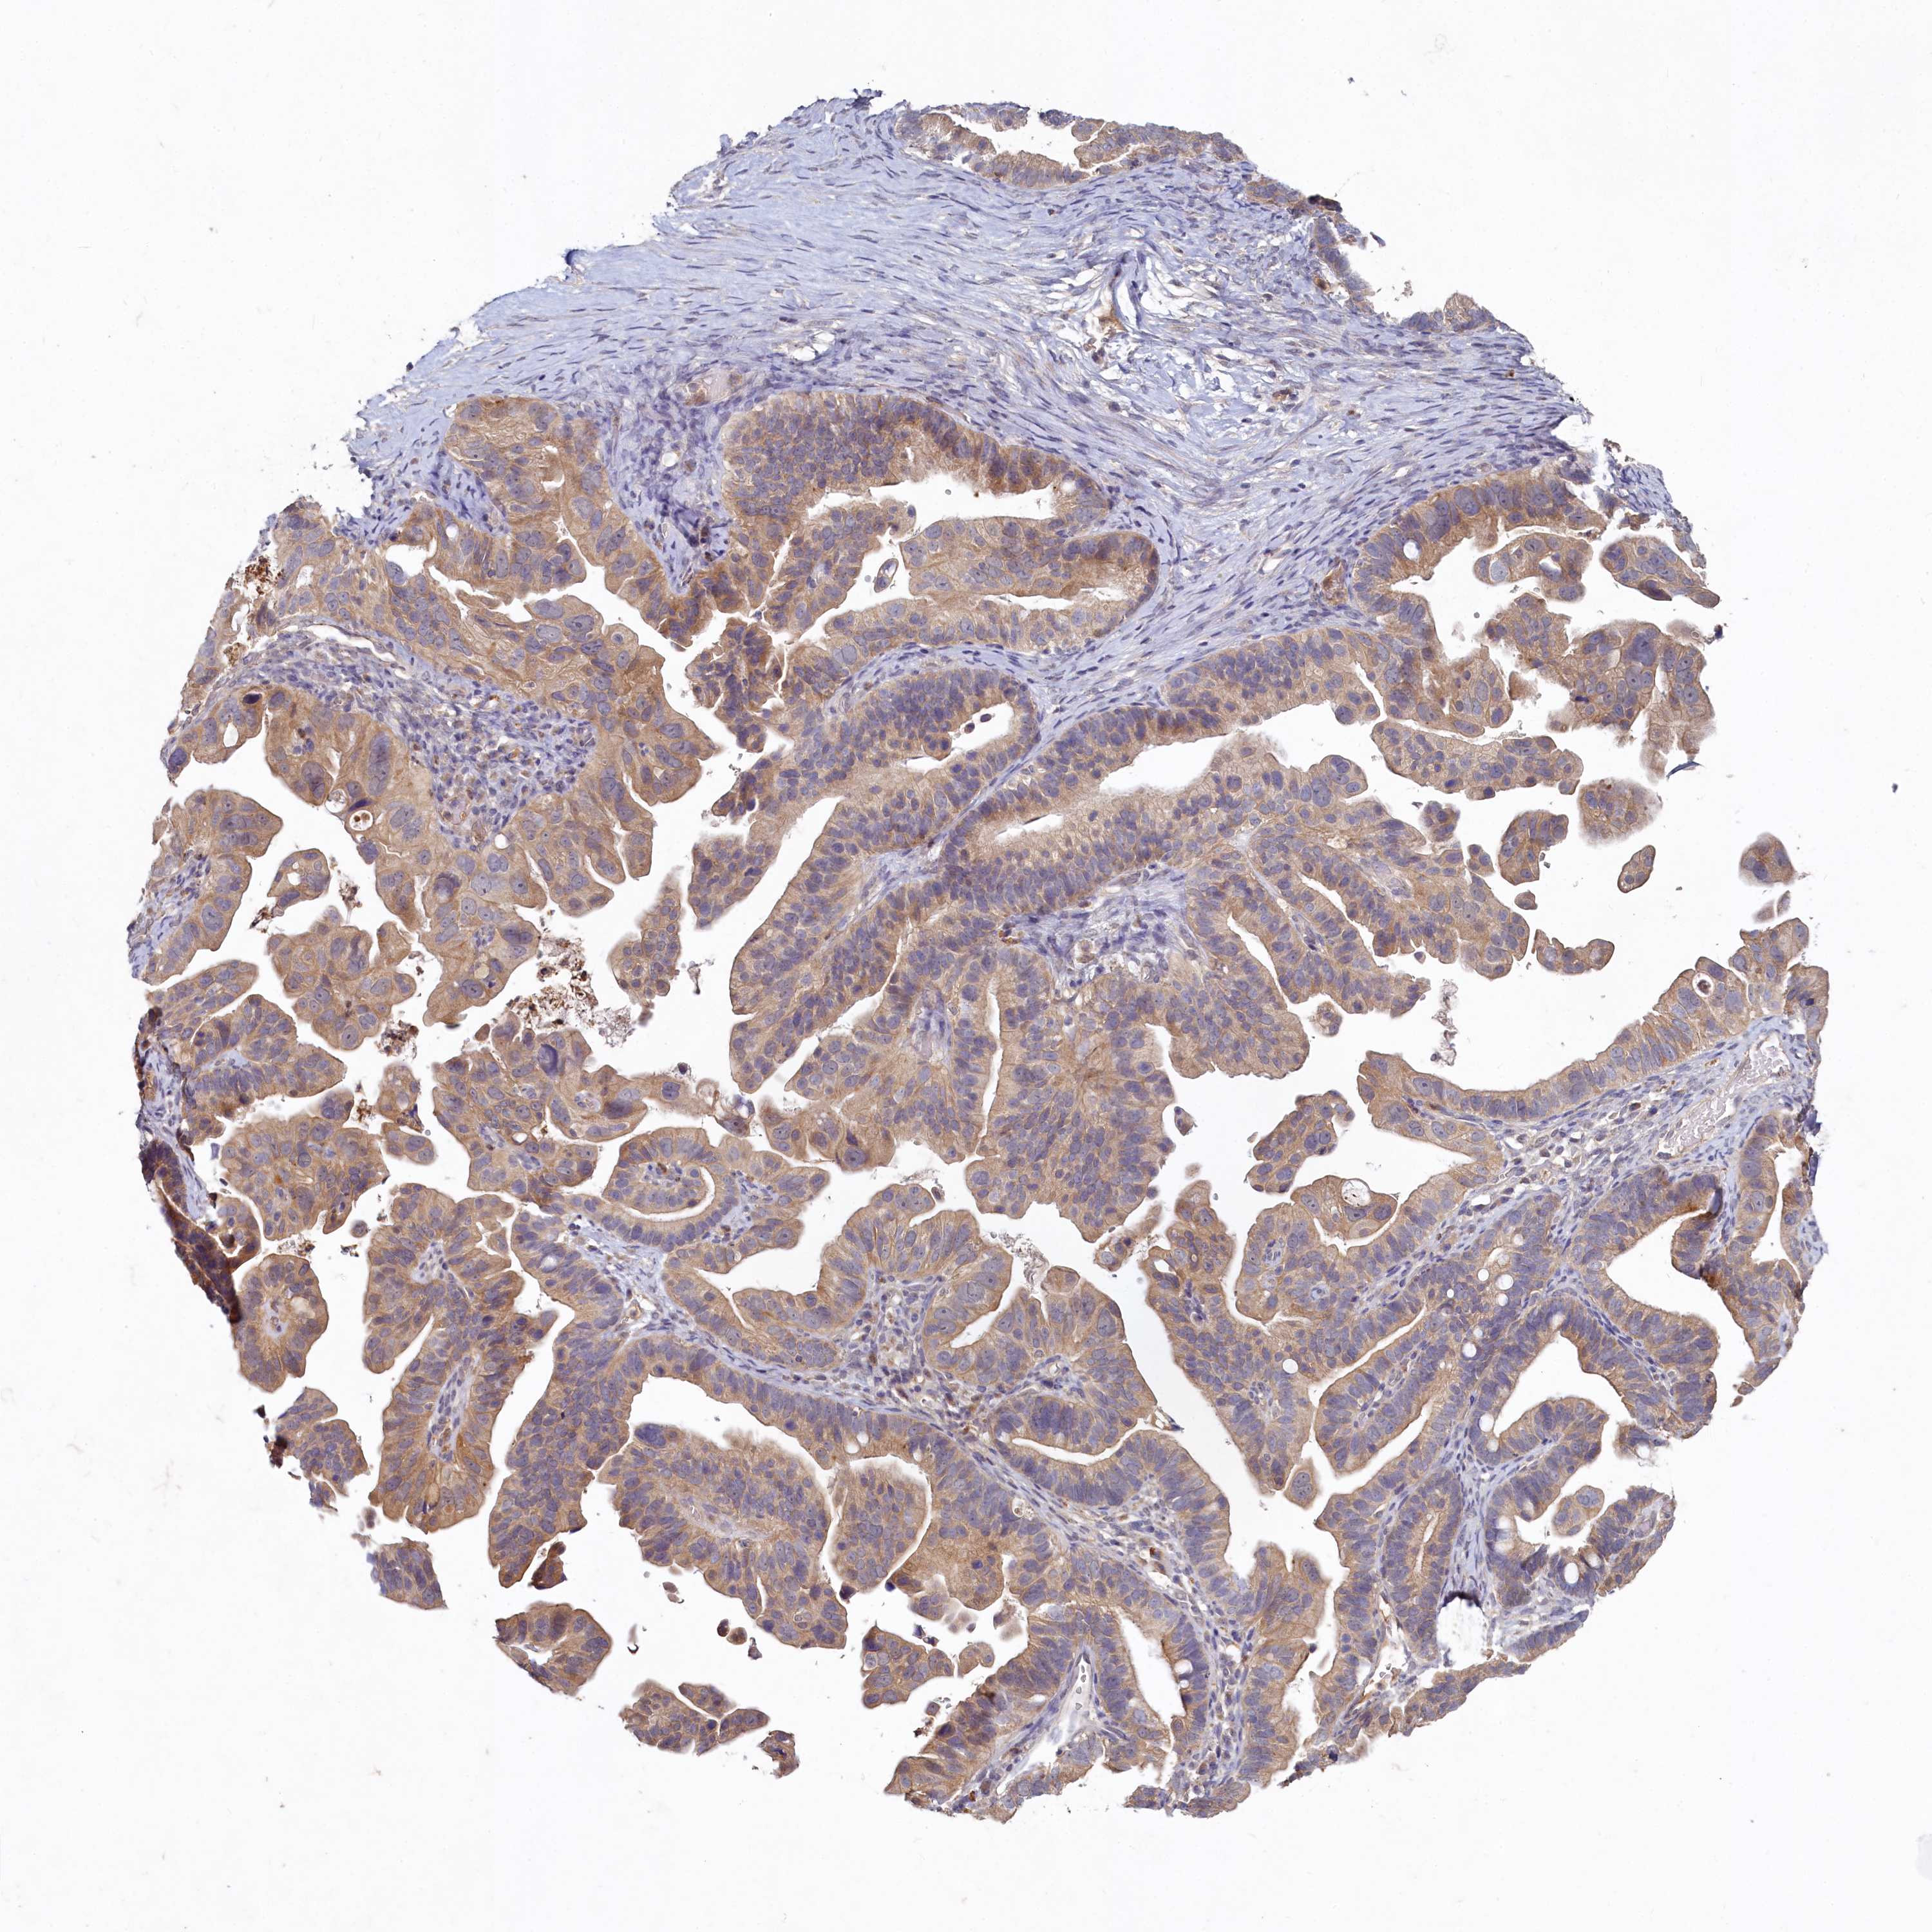

OVARIAN CANCER - Protein expressioni

A mouse-over function shows sample information and annotation data. Click on an image to view it in a full screen mode. Samples can be filtered based on level of antibody staining by selecting one or several of the following categories: high, medium, low and not detected. The assay and annotation is described here.

Note that samples used for immunohistochemistry by the Human Protein Atlas do not correspond to samples in the TCGA dataset.

Antibody stainingi

Antibody staining in the annotated cell types in the current human tissue is reported as not detected, low, medium, or high, based on conventional immunohistochemistry profiling in selected tissues. This score is based on the combination of the staining intensity and fraction of stained cells.

Each image is clickable and will lead to virtual microscopy that enables deeper exploration of all samples and also displays staining intensity scores, fraction scores and subcellular localization as well as patient and tissue information for each sample.

Antibody HPA039170

Staining

High

Medium

Low

Not detected

Intensity

Strong

Moderate

Weak

Negative

Quantity

>75%

75%-25%

<25%

None

Location

Nuclear

Cytoplasmic/membranous

Cytoplasmic/membranous,nuclear

Cystadenocarcinoma, serous, NOS

Carcinoma, endometroid

Cystadenocarcinoma, mucinous, NOS

Carcinoma, NOS